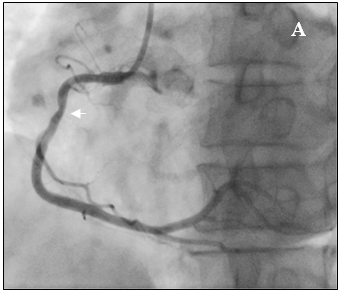

Tại cấp cứu bệnh nhân được chẩn đoán nhồi máu cơ tim cấp vùng hoành giờ thứ 2, block A-V độ 3, có chỉ định chụp mạch vành cấp cứu. Kết quả chụp mạch vành cho thấy hẹp nặng lan tỏa nhiều đoạn ở cả động mạch vành trái (hình 2a) và động mạch vành phải (hình 2b).

Hình 2a: Dấu mũi tên trắng cho thấy nhiều chổ hẹp ở nhánh LCX, OM và LAD

Hình 2b: Hệ mạch vành ưu thế phải, hẹp lan tỏa RCA